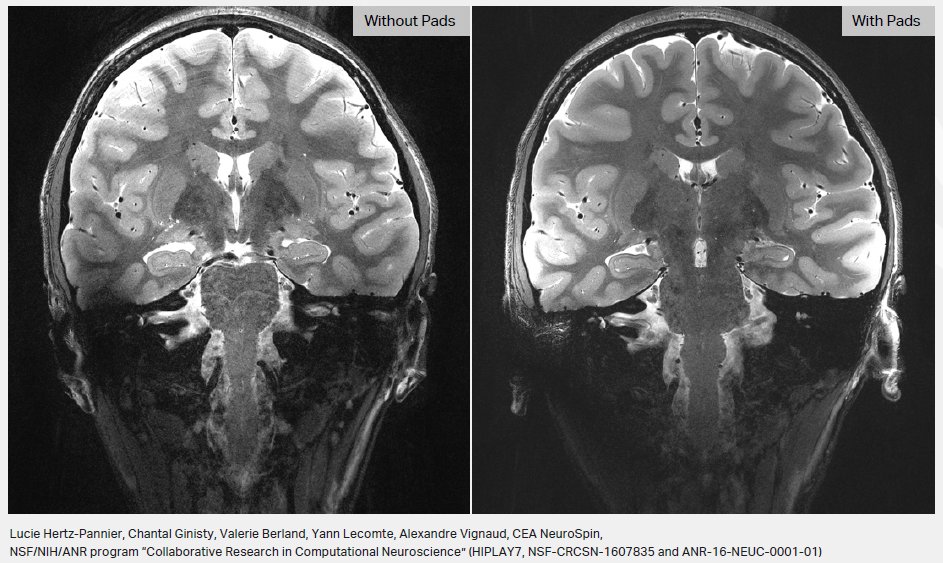

👍A real difference with and without Pads as you can see ! 🙏Special Thanks to @VignaudAlexand4 & all the #CEA team @NeuroSpin_91 @CEA_Joliot Discover the #MRIpads for 7T and Metapads (>=3T) with @MultiwaveI @MultiwaveT team at #RSNA20 conference